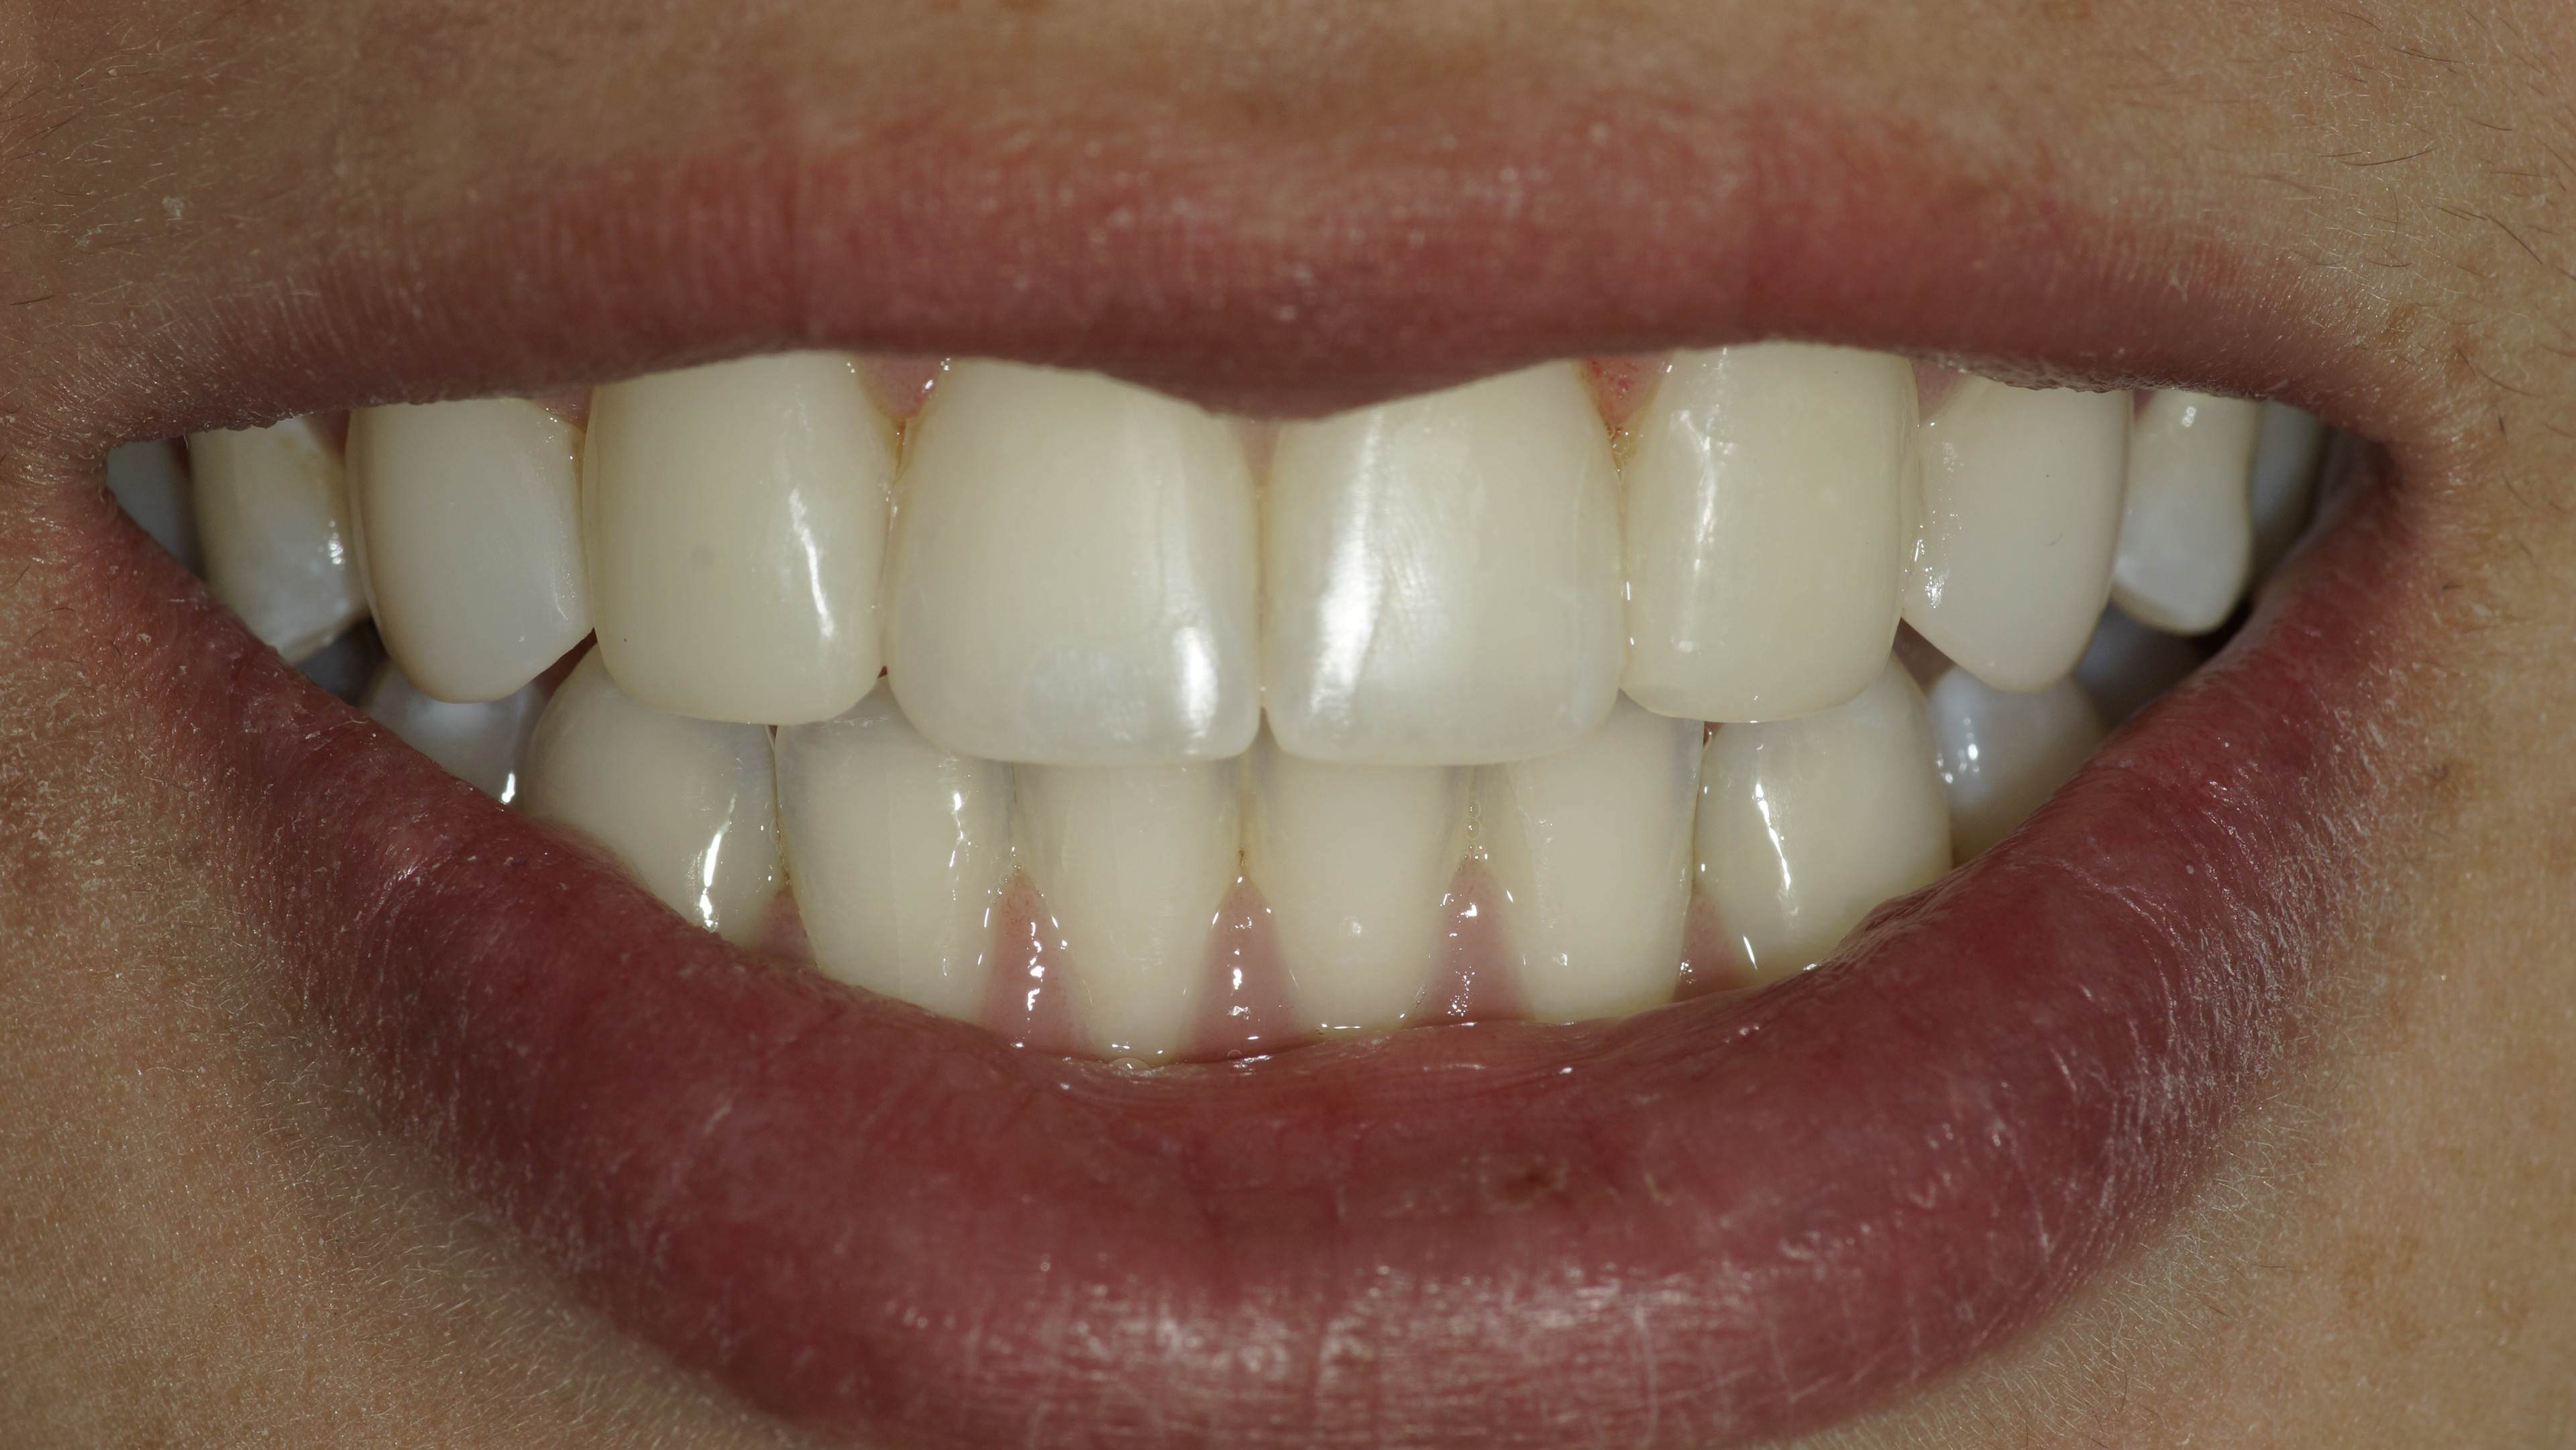

After

E-max Final post-op

Immediate port-op - Nice shade